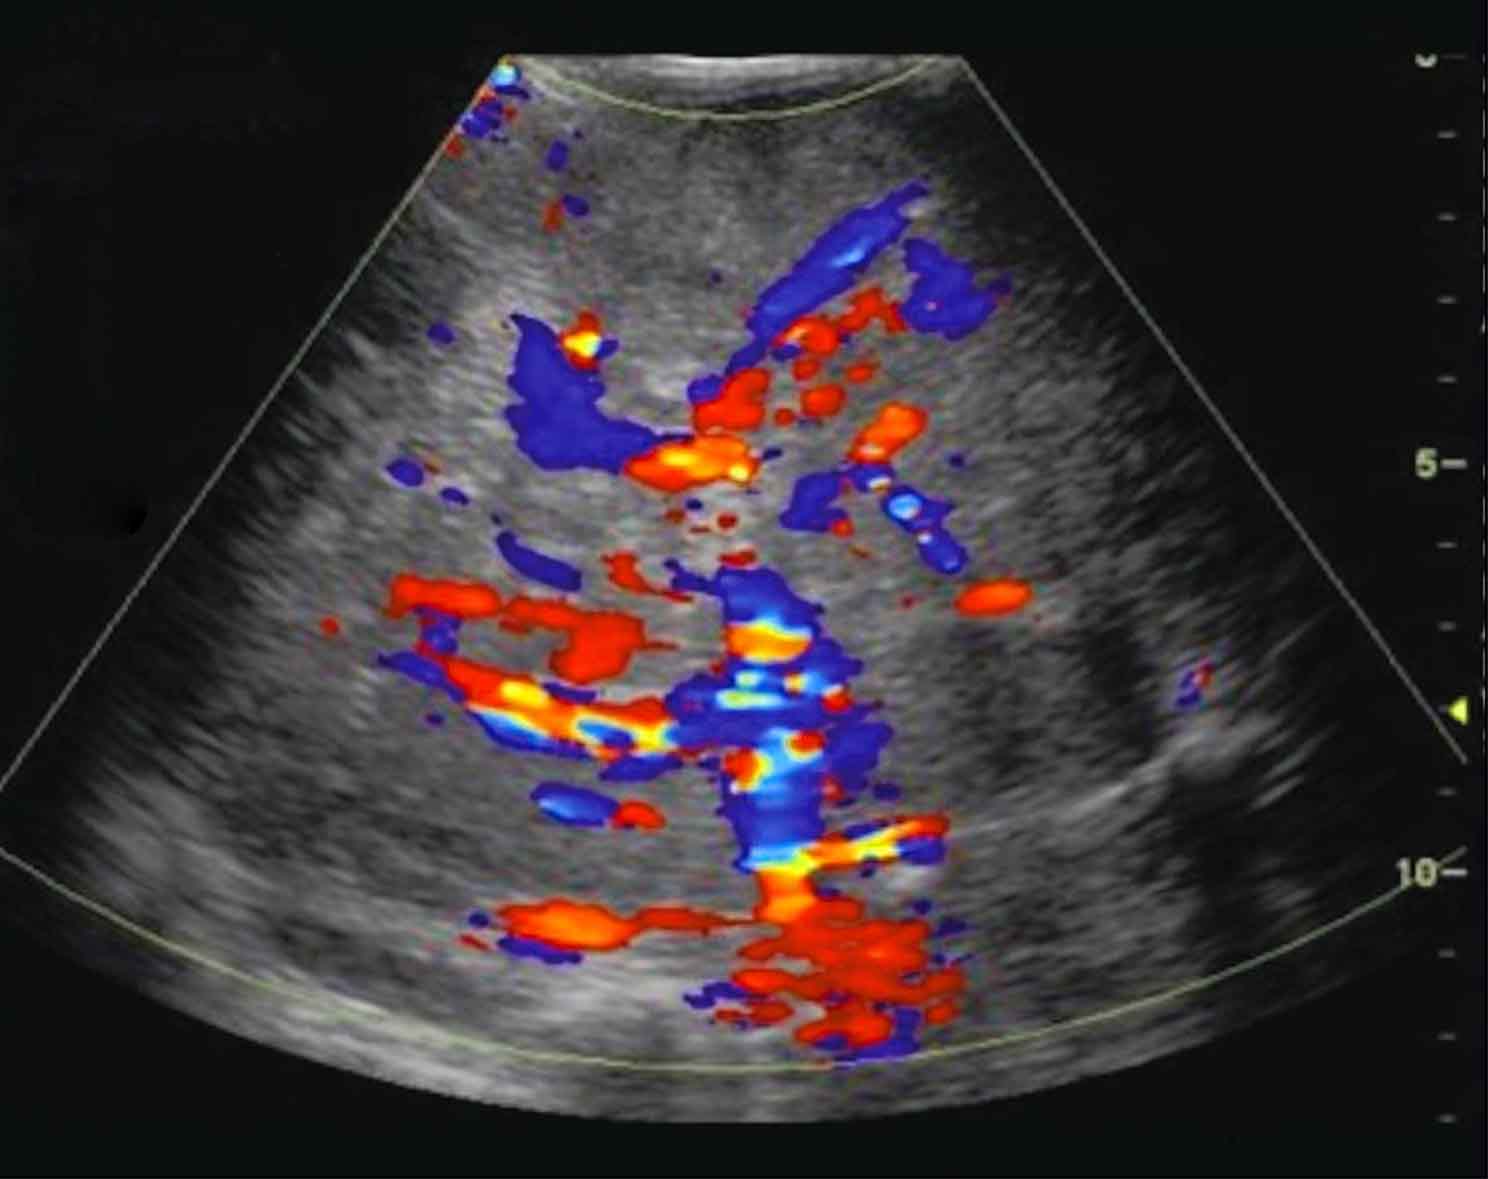

Cisti Renali

Una cisti è una sacca, generalmente ripiena di liquido, delimitata da una parete che separa il contenuto da ciò che circonda la cisti stessa. La cisti renale semplice di per sé è una lesione benigna. A volte possono essere associate a disturbi potenzialmente dannosi per la funzione renale o per l’organismo. Le cisti del rene possono essere lasciate in sede senza…